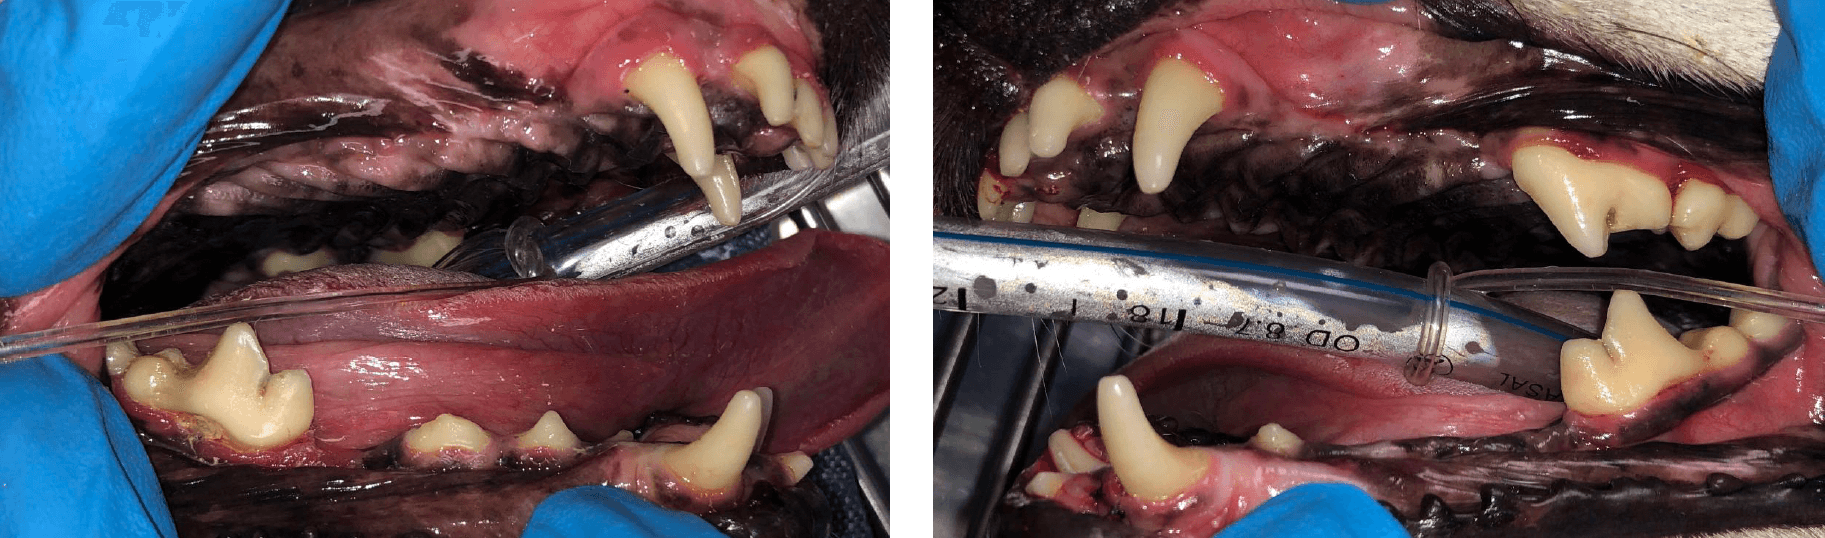

Below: Presentation at the beginning of procedure with RDVM

Below: After procedure with RDVM (Before referral to Animal Dentistry Referral Services)

In the one month after the referring DVM performed closed root planing, the upper right canine palatal pocket had improved from 5mm to 3mm (within normal limits) and the upper left canine infra-bony pocket depth had also improved from 8mm to 6mm. It’s typical to have a 1-2mm improvement in probing depth in the short term (1-3 months). Closed root planing turns an active periodontal pocket inactive. Recurrence of active periodontal disease is dependent up on pocket depth and dental home care as well as sooner (3-6 months) professional anesthetic dental procedures.